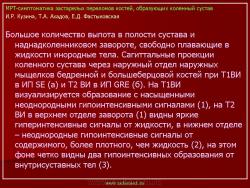

Магнитнорезонансная томография в диагностике повреждений костей голеностопного сустава.

Семиотика стресс-переломов аналогична скрытым переломам костей голеностопного сустава и стопы. Дополнительно визуализируется периостальная реакция. Однако в отличие от скрытых переломов патологические изменения визуализируются и рентгенологически.

При проведении МРТ больным с переломами костей голеностопного сустава и стопы не ставится задача оценки переломов. Изучается состояние сухожильно-связочного аппарата и параартикулярных мягких тканей. Гипсовые повязки не оказывают существенного влияния на качество и информативность изображений.